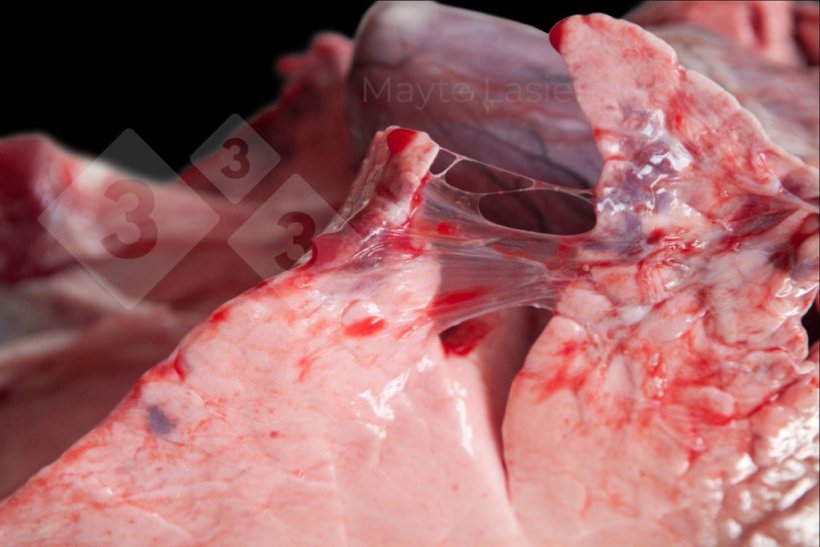

Zapalenie opłucnej występuje często i obejmuje zmiany chorobowe w dogrzbietowo-doogonowej części płuca, związane głównie z podostrą lub przewlekłą postacią zapalenia opłucnej świń (APP). Objawia się białymi plamami na opłucnej trzewnej płatów przeponowych, odpowiadającymi złogom włóknika.

Zapalenie opłucnej może również występować w obszarach doczaszkowych płuc, powodując zrosty między sąsiednimi płatami płucnymi. Zazwyczaj towarzyszą mu koinfecje pochodzenia bakteryjnego (Pasteurella multocida, Glaesserella parasuis, Streptococcus suis itp.) i nazywane są zapaleniem opłucnej doczaszkowej, aby odróżnić je od zapalenia opłucnej związanego z APP.